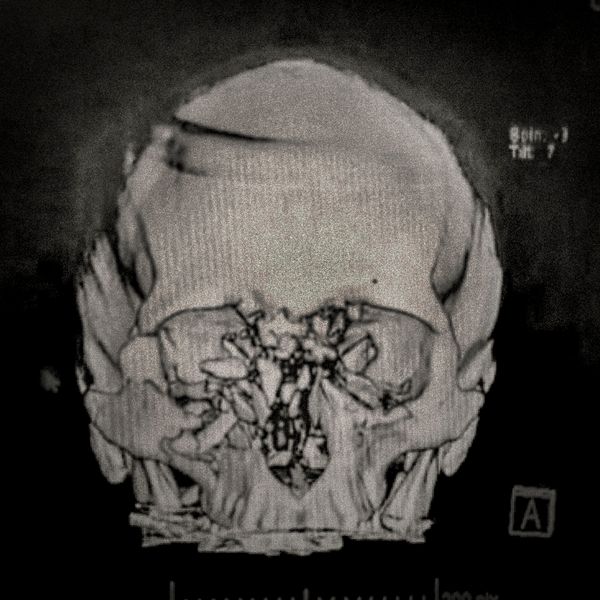

460 people have been seriously injured in their eyes, 34 of whom suffered total loss due to the indiscriminate use of pellets and tear gas bombs by the Carabineros de Chile special forces. The Carabin

460 people have been seriously injured in their eyes, 34 of whom suffered total loss due to the indiscriminate use of pellets and tear gas bombs by the Carabineros de Chile special forces. The Carabineros fired their rubber bullets and tear gas guns directly into the faces of the protesters during the Chilean social outbreak between late 2019 and early 2020. This figure has made Chile the country with the world record for eye mutilation by state and security forces.

By early March 2020, around 3,838 people had been injured and according to the Chilean Society of Ophthalmologists and human rights organizations, 460 of them ended up with serious eye complications, loss of the eyeball, and also loss of sight. This figure has made Chile a world record for eye mutilation, due to the indiscriminate use of pellets and tear gas bombs by special forces of the Carabineros, who have shot their weapons directly into the faces of the protesters.